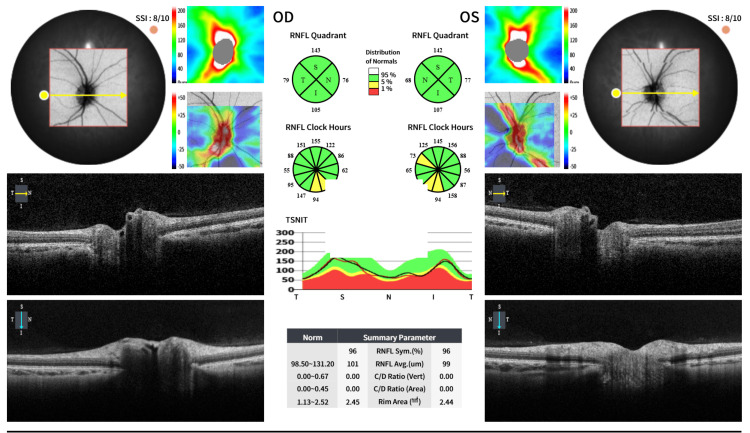

特发性颅内高压(IIH)和多囊卵巢综合征(PCOS)与育龄妇女肥胖密切相关。胰高血糖素样肽-1受体激动剂(GLP-1 RAs)已被广泛报道通过中枢饱腹感促进体重减轻。新出现的证据表明GLP-1 RAs具有额外的益处。艾塞那肽直接作用于脉络膜丛受体,减少脑脊液(CSF)分泌和颅内压(ICP),并作用于卵巢,促进卵泡成熟,恢复排卵,改善PCOS患者的生育结局。一位29岁女性多囊卵巢综合征被转介到妇科评估间歇性视力模糊和慢性头痛。眼科检查单眼视力正常6/5,双眼视力下降6/12,伴重影。据报道,她在8个月内体重增加了15公斤。眼底镜检查无明显异常,无视盘肿胀。无乳头水肿(iihop)的诊断是基于磁共振成像显示垂体窝增大,部分鞍空,视神经鞘扩张,腰椎穿刺证实开口压力升高280 mmH₂O,脑脊液正常。最初使用乙酰唑胺治疗因不耐受而停止。随后开始使用艾塞那肽,导致头痛频率和复视的早期改善,独立于体重减轻。月经周期、激素水平和胰岛素抵抗的改善也超出了单用二甲双胍的效果。该病例强调了艾塞那肽在IIH和PCOS中提供双重治疗益处的潜力,通过直接受体介导的途径降低ICP,改善头痛,恢复排卵周期,并间接通过减少中心性肥胖。有必要进行进一步的研究,以确定其在这些条件的联合管理中的作用。

Idiopathic intracranial hypertension (IIH) and polycystic ovary syndrome (PCOS) are strongly associated with obesity in women of reproductive age. Glucagon-like peptide-1 receptor agonists (GLP-1 RAs) have been extensively reported to facilitate weight loss through central satiety. Emerging evidence demonstrates additional benefits of GLP-1 RAs. Exenatide exerts direct effects on choroid plexus receptors, reducing cerebrospinal fluid (CSF) secretion and intracranial pressure (ICP), and on the ovary, enhancing follicular maturation, restoring ovulation, and improving fertility outcomes in PCOS. A 29-year-old woman with PCOS was referred from gynecology for assessment of intermittent visual blurring and chronic headaches. Ophthalmic examination revealed normal monocular visual acuity of 6/5 in each eye but reduced binocular vision of 6/12, associated with double vision. She also reported a weight gain of 15 kg over eight months. Fundoscopy was unremarkable, with no optic disc swelling. IIH without papilledema (IIHWOP) was diagnosed based on magnetic resonance imaging showing an enlarged pituitary fossa, partial empty sella, and optic nerve sheath dilatation, with lumbar puncture confirming a raised opening pressure of 280 mmH₂O and normal CSF. Initial treatment with acetazolamide was discontinued due to intolerance. Exenatide was subsequently initiated, leading to early improvement in headache frequency and diplopia, independent of weight loss. Menstrual cycles, hormonal profile, and insulin resistance also improved beyond the effect of metformin alone. This case highlights the potential of exenatide to provide dual therapeutic benefits in IIH and PCOS, acting through direct receptor-mediated pathways to reduce ICP, improve headaches, and restore ovulatory cycles, and indirectly through the reduction of central obesity. Further studies are warranted to establish its role in the combined management of these conditions.